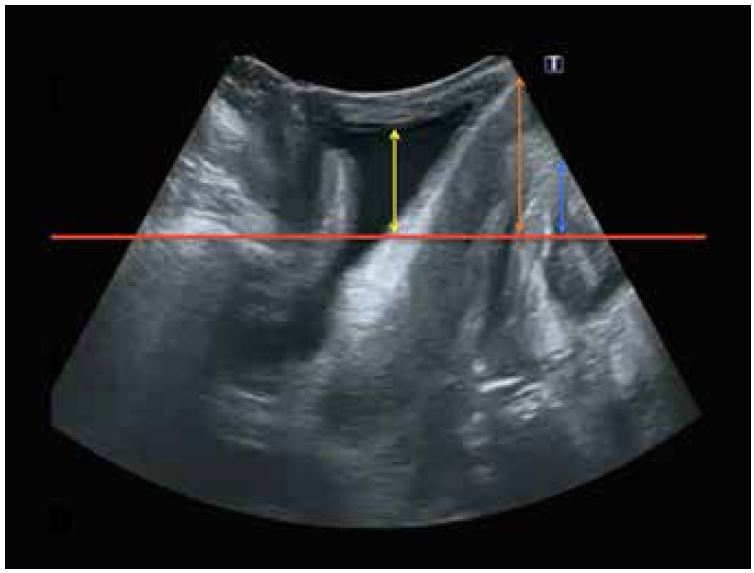

Пролапс тазових органів визначається як опущення органів малого таза з порожнини малого тазу, яке може охоплювати передню стінку піхви або сечовий міхур, задню або пряму кишкову стінку піхви, матку або звід піхви. Для ультразвукової оцінки POP вимірювання проводять від контрольної точки, встановленої уявною лінією (червона лінія на мал. 5), що проходить повз задньонижній край лобкового симфізу. POP є суттєво симптоматичним, якщо воно перевищує базову лінію на 10 мм у передньому відділі (жовта лінія на мал. 5) або на 15 мм у середньому (помаранчева лінія на мал 5) і задньому відділі (синя лінія на мал. 5).

Малюнок 5. Базова лінія, яка проходить повз задньонижній край лобкового симфізу (червона лінія). Пролапс тазових органів (POP) переднього (жовта стрілка), середнього (помаранчева стрілка) і заднього відділів